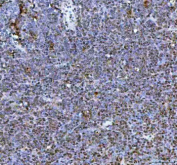

Immunohistochemical staining of NR1D2 using anti-NR1D2 antibody. NR1D2 was detected in a paraffin-embedded section of human cancer tissue. Heat mediated antigen retrieval was performed in EDTA buffer (pH 8.0, epitope retrieval solution). The tissue section was blocked with 10% goat serum. The tissue section was then incubated with 2 ug/ml rabbit anti-NR1D2 antibody overnight at 4oC. Peroxidase Conjugated Goat Anti-rabbit IgG was used as secondary antibody and incubated for 30 minutes at 37oC. The tissue section was developed using an HRP secondary and DAB substrate.